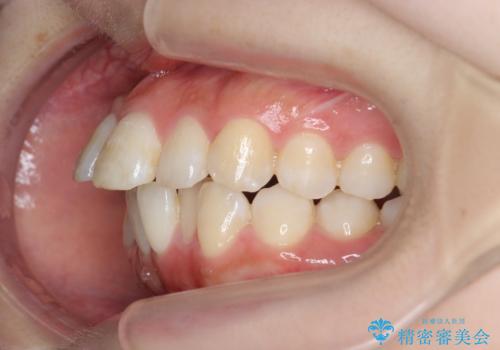

インビザラインで出っ歯の治療

- 「目立つ前歯の出っ歯をなんとかしてほしい。」と矯正治療を希望され来院されました。

突出した上顎の前歯に加え、ガタつきの目立つ下顎の歯列も同時にマウスピース矯正インビザラインで整えていきます。

突出間(所謂 出っ歯)のある前歯の位置は大幅に改善され、審美性が大きく向上しました。

加えて奥歯も噛み合わせも良くなったことで、咬合状態が安定しより安定した歯列を獲得することができました。